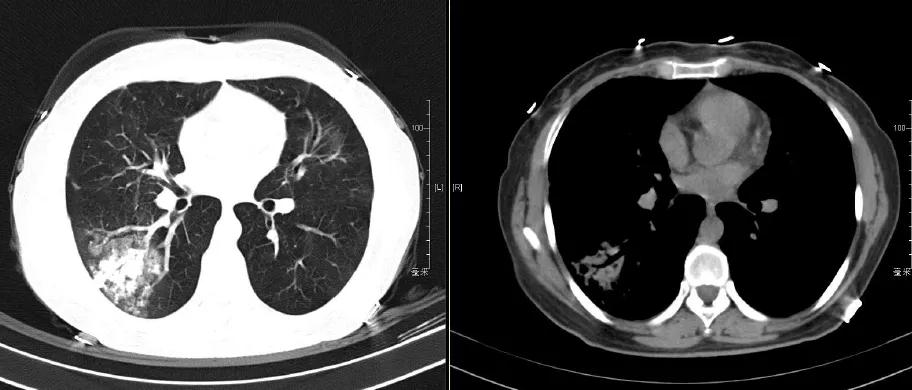

(1)抗结核治疗1月后随访胸部CT:

(2)抗结核治疗1年随访胸部CT:

开始予四联抗结核:异烟肼0.3g qd po,利福平0.45g qd po,乙胺丁醇0.75g qd po,吡嗪酰胺0.5g tid po

停用硫唑嘌呤;糖皮质激素逐步减量至停用。